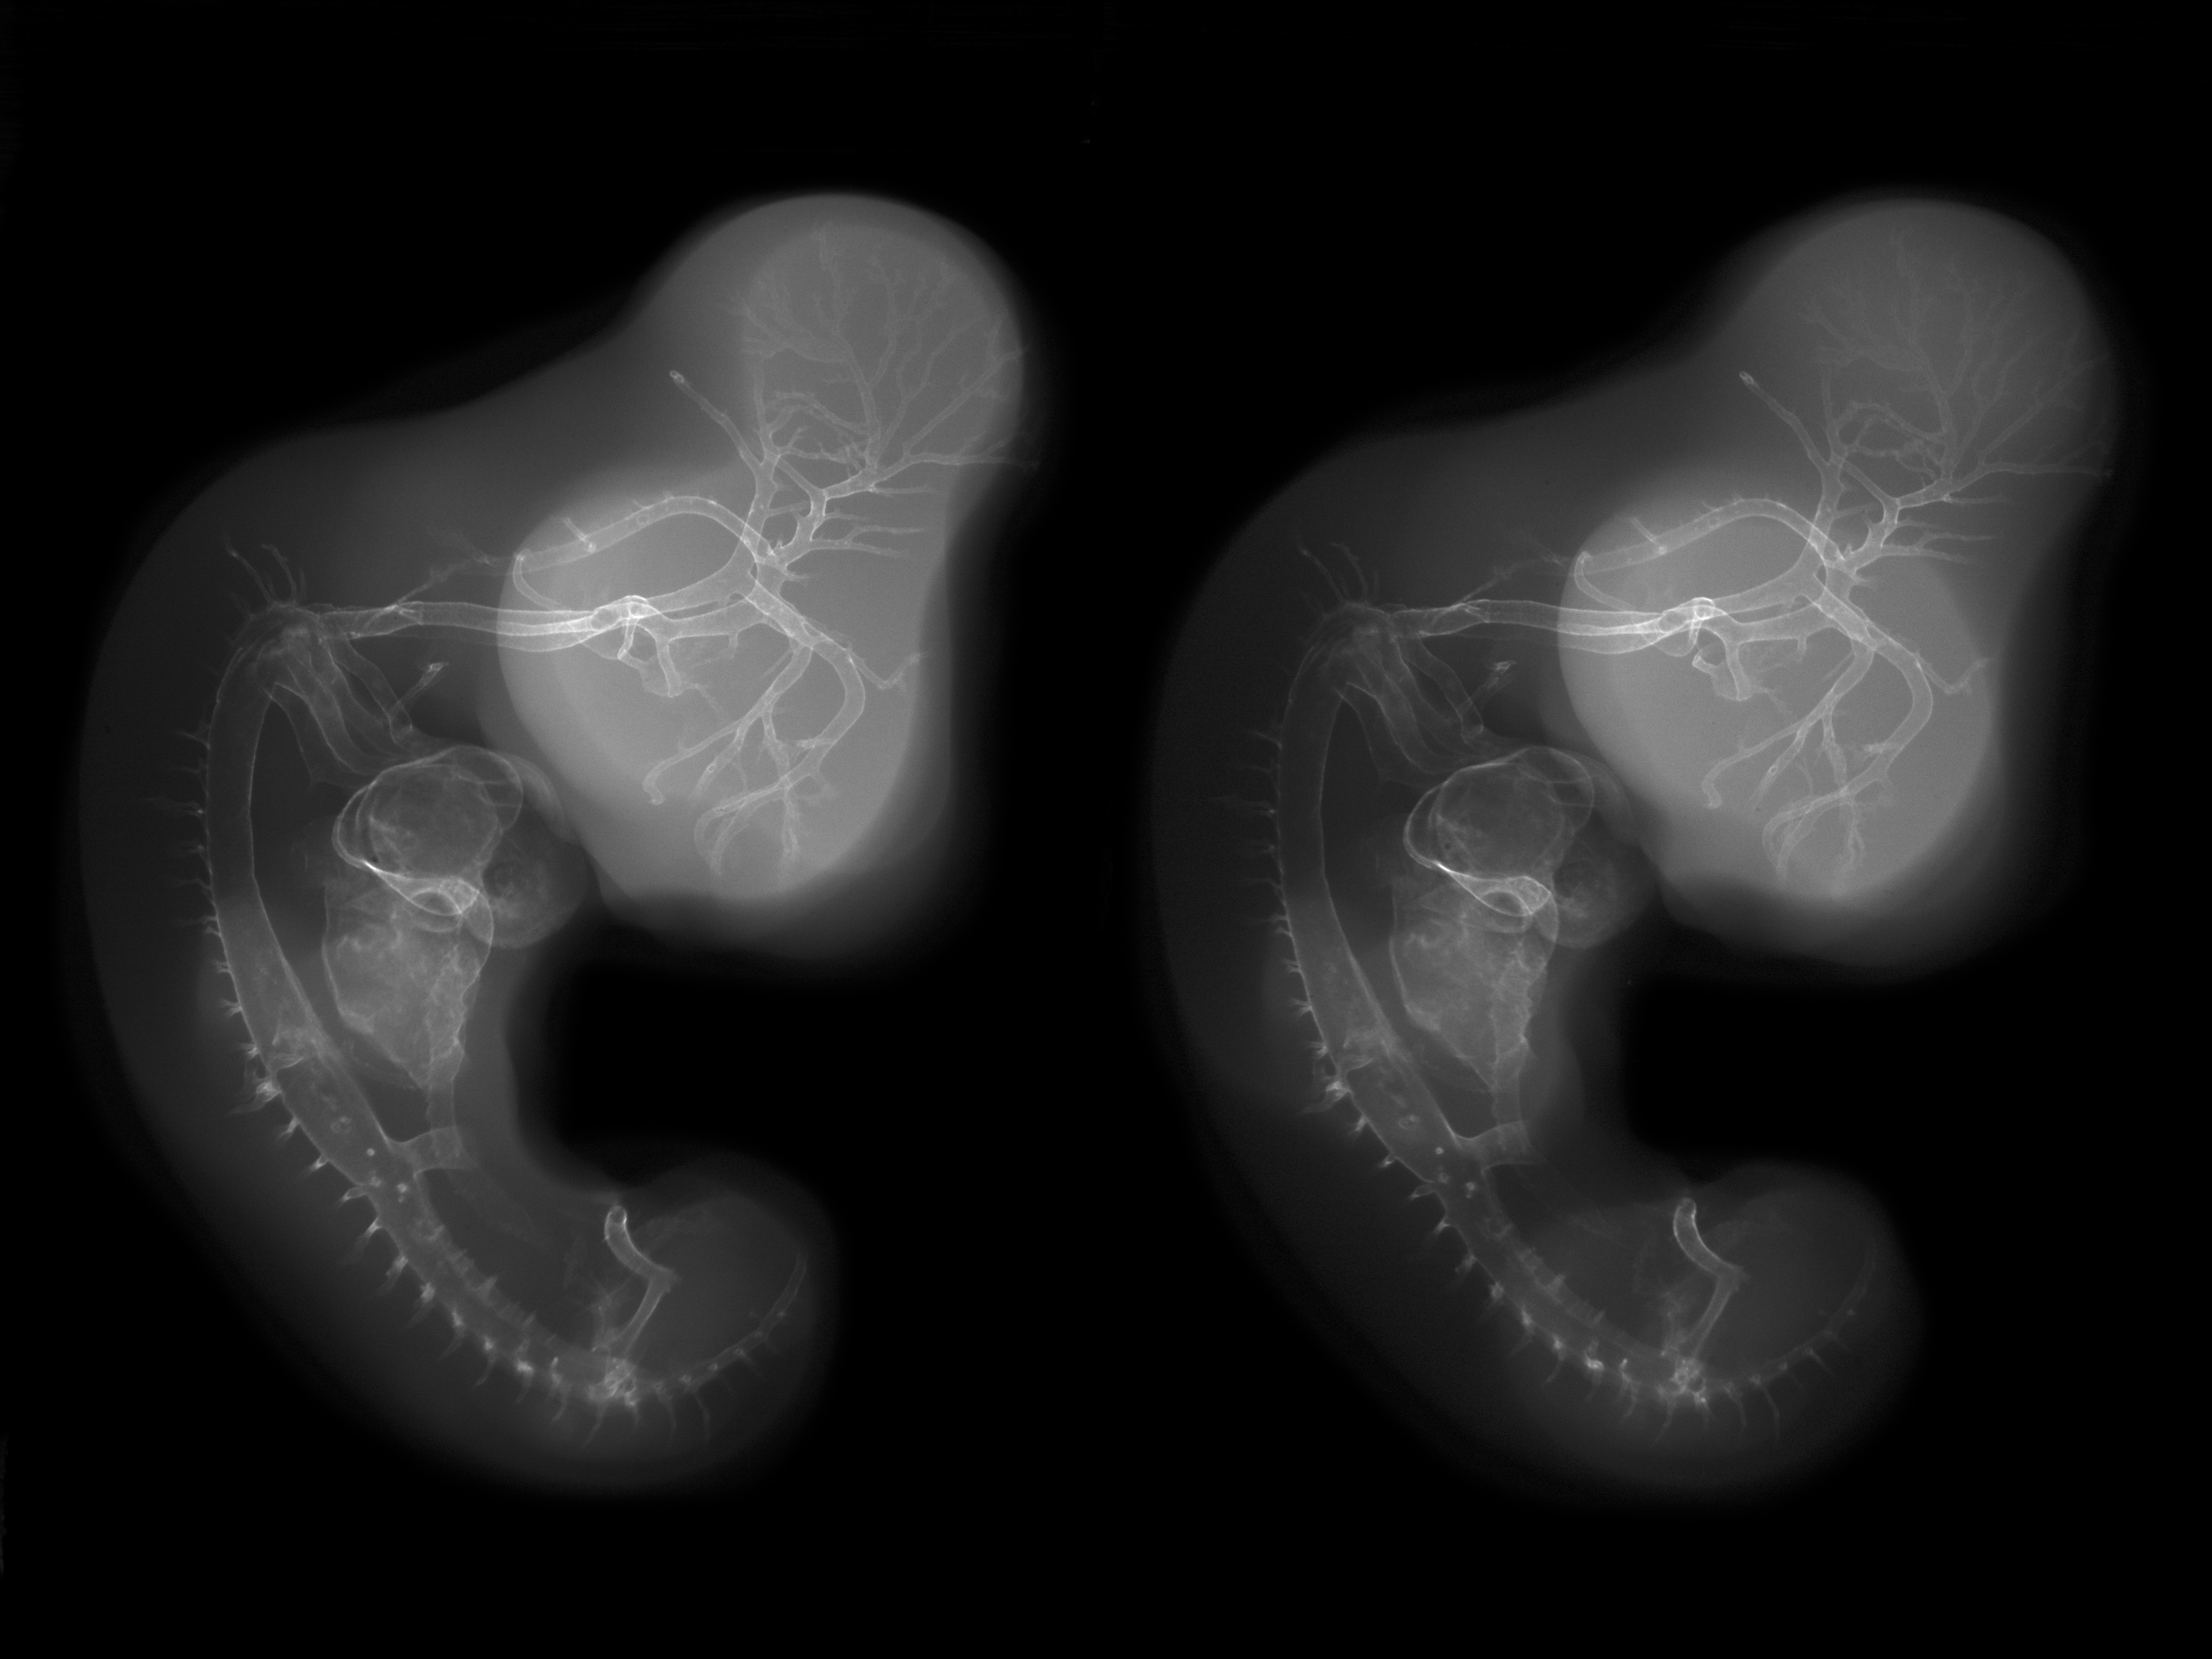

Stereo X-Ray Micrographs